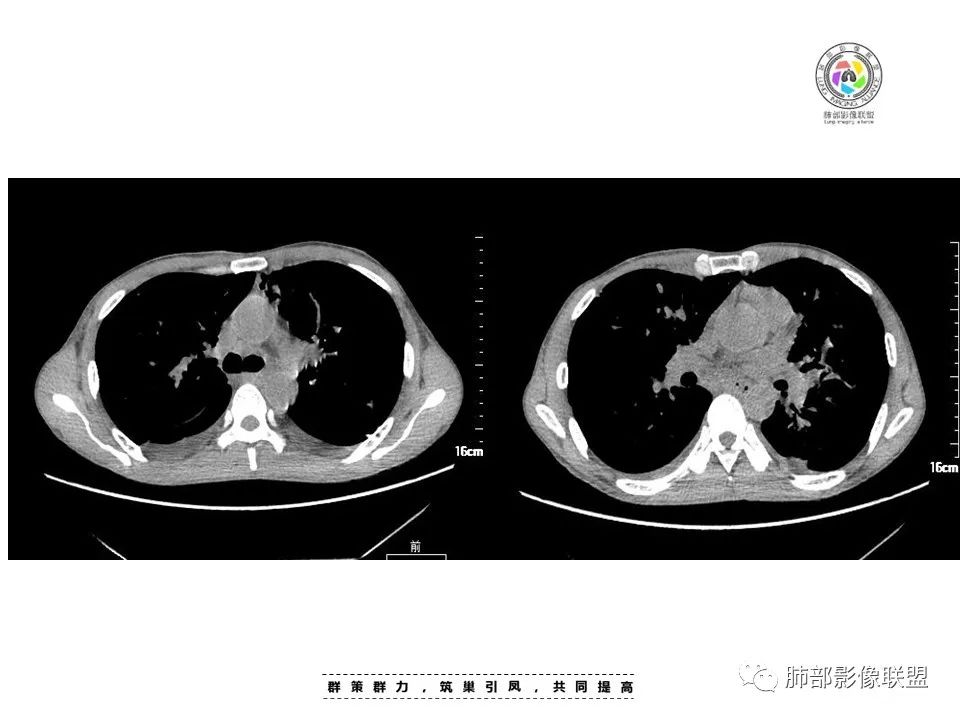

周一晚读病例:男性45岁,发热、纳差,全身散在暗紫色皮疹,结合CD4,符合HIV;肺部影像表现:两肺散在实性结节及磨玻璃密度影,实性结节伴晕征,部分沿支气管血管束分布,支气管血管束增粗,以两肺下叶为著,类似火焰征,双侧胸腔少量积液;首先考虑卡波西肉瘤,鉴别淋巴瘤增值性病变,淋巴瘤样肉芽肿/淋巴瘤,最后挂上马尔尼菲青霉菌病。

中年男性,发热、全身散在暗紫色丘疹,查CD4+T细胞64个/ul,临床信息提示AIDS并发卡波西肉瘤;CT提示双肺多发实性结节影及毛玻璃结节,部分呈点晕征,右上肺大姐姐边缘膨隆、分叶伴晕;双下肺结节沿支气管血管束分布,中轴间质增粗,部分支气管堵塞,叶间裂结节状增厚,部分结节胸膜下分布,可疑局部小叶间隔增厚,肺部病变呈淋巴分布特点,结合临床肺部病变考虑肺卡波西肉瘤,鉴别淋巴瘤。

两肺弥漫性性结节状、小片状及片状带晕的病灶,煎蛋征、点晕征,主要分布两肺中下叶,病灶周围小叶间隔增厚呈网格状影,部分病灶累及胸膜,伴两侧胸膜增厚。

2.本例双肺小叶间隔增厚明显,多发结节影及片状实性密度影,沿血管支气管束分布为主,两侧较为对称,病灶多环以磨玻璃晕,边界不清。

双侧胸腔少量积液。双肺门及纵隔未见明确肿大淋巴结,纵隔结构间隙模糊。

3.有学者将这种具有沿双肺支气管束分布的实性密度片影描述为“火焰征”,认为具有一定特征性,单就影像表现而言,这种影像表现也可以见于其他病损或多种病理改变的叠加。

1.结节型:两肺沿支气管血管束分布的结节影,呈火焰状或星芒状、挂果征,局部周围出血磨玻璃影(肺泡出血或水肿)。

2.支气管血管束增粗型:

肺门周围支气管壁呈“套袖样”改变。

3.肺炎渗出型:

斑片渗出影,部分融合呈“火焰样”,同时有火焰样结节,小叶间隔增厚等表现。

还可以有纵隔及腋下淋巴结增大,胸腔积液等表现。